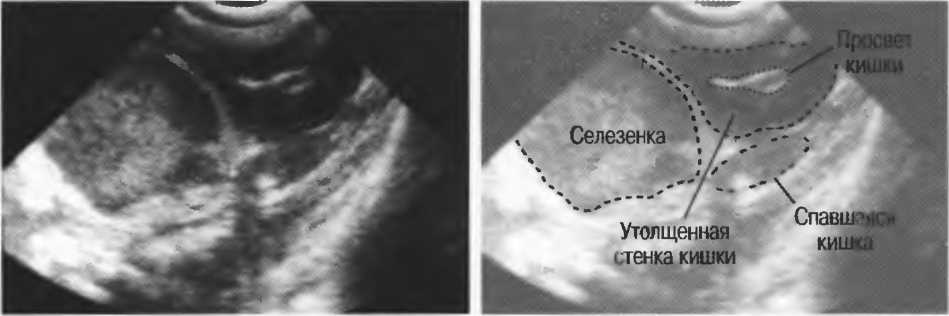

1. Подготовка

Пациент не должен пить и есть в течение 8 ч перед исследованием. Если жидкость необходима для предотвращения дегидратации, можно давать пациенту только воду. При острой симптоматике исследование можно проводить без подготовки. Детям, если позволяют клинические условия, пища и вода не даются в течение 3 ч до исследования.

При более углубленном исследовании, если нет клинических противопоказаний, может быть полезным дополнительный прием воды, особенно при исследовании поджелудочной железы, нижних отделов живота и таза.

2. Положение пациента. Пациент может лежать в удобной позе на спине. Под голову можно положить маленькую подушку, в случае выраженного напряжения передней брюшной стенки подушечку можно поместить также под колени пациента.

Намажьте живот гелем.

Пациенту разрешается дышать спокойно, однако при исследовании отдельных органов требуется задержка дыхания на вдохе.

3. Выбор датчика. Используйте датчик 3,5 МГц для взрослых и датчик 5 МГц для детей и худых взрослых. Предпочтительны конвексные или секторные датчики.

4. Установите правильный уровень общей чувствительности. Начинайте исследования, поместив датчик центрально в верхней части живота под мечевидным отростком и попросите пациента глубоко вдохнуть и задержать дыхание на вдохе.

Поверните датчик направо до того, как начнет визуализироваться печень. Отрегулируйте чувствительность, чтобы изображение имело нормальную однородную зхоструктуру. Должна быть хорошо различима высокоэхогенная линия диафрагмы сразу за задними отделами печени (рис. 27а).

Воротная и печеночные вены должны визуализироваться как трубчатые структуры с анзхогенным просветом. Стенки воротной вены высокозхогенны, но стенки печеночных вен практически не видны (рис. 276).

Рис.27а. Продольный срез. Неизмененная печень и диафрагма.